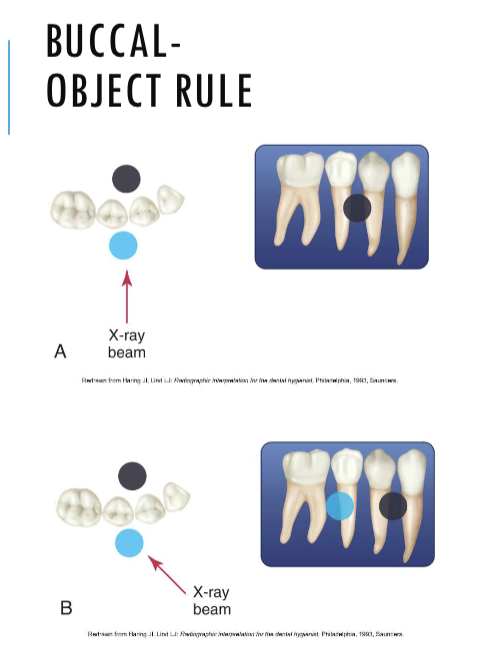

buccal object rule

expose 1st image (PA or bw)

take a second image with a different H or V angulation aka same area different angle

compare images to see how the object shifted in the image

SLOB

lingual

buccal

lingual

lingual

buccal